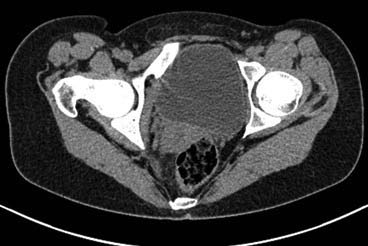

Здравствуйте.Помогите с диагнозом и тактикой лечения.

Больная 15 лет. Жалобы: на укорочение правой нижней конечности, хромоту. Анамнез: Со слов

болеет с детства, травму отрицает. Ранее за медицинской помощью не обращалась. Последние 2

года отмечает резкое укорочение конечности. Локально: При осмотре отмечается умеренное

искривление позвоночника во фронтальной плоскости, умеренная асимметрия лопаток и

надплечий. Скошенность таза. Отмечается укорочение правой нижней конечности на 3 см.

Движения в тазобедренном и коленном суставах в полном объеме. Нейрососудистых нарушений в

периферических отделах нет.